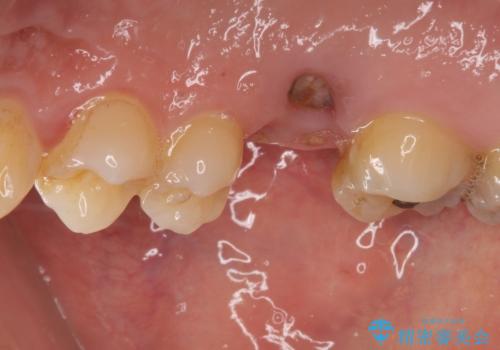

反対側の歯は、歯根だけが歯肉に埋もれて残っている状態のため、抜歯が必要な状態でした。

歯根だけとなっている歯はインプラントに、神経組織の失活している歯は根管治療を行い、いずれもオールセラミッククラウンにて補綴治療を行うこととしました。